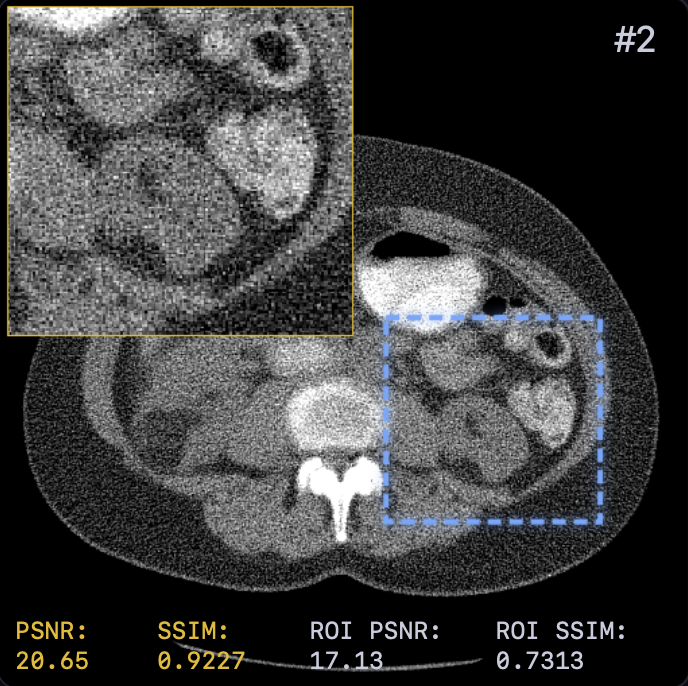

Table I presents the quantitative comparison. LTV achieves the best overall performance, surpassing FBP+U-Net [5] by approximately dB PSNR. Notably, learning the solver dynamics yields a consistent gain ( dB PSNR) over the fixed-solver baseline (29.42 vs. 30.15 dB). This confirms that end-to-end optimization of step sizes and relaxation provides modeling capacity beyond spatial adaptivity alone.

Qualitative results (Fig. 2) demonstrate that LTV preserves fine structures (e.g., vessel continuity) while avoiding the over-smoothing of classical TV and the anatomical inconsistencies of FBP+U-Net. This is corroborated by the error maps in Fig. 3, where LTV exhibits smaller and more spatially uniform residuals, indicating a balanced trade-off between noise suppression and detail preservation.